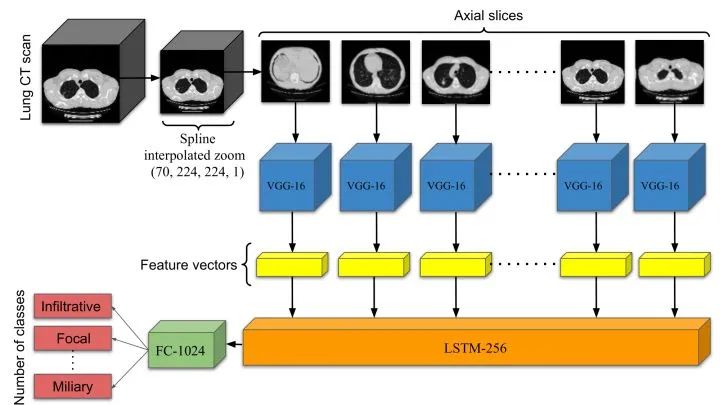

ViPTT-Net: Video pretraining of spatio-temporal model for tuberculosis type classification from chest CT scans

来自康考迪亚大学&North South University

ViPTT-Net,在 1300 多个带有人类活动标签的视频片段上进行训练,然后在带有结核病类型标签的胸部 CT 扫描上进行微调。发现,在视频上预训练模型表现更好,并大大改善了模型的验证性能,kappa score 从 0.17 到 0.35,特别是对于代表性不足的类别样本。其中最好的方法在 ImageCLEF 2021 结核病-TBT分类任务中获得了第二名,在只有图像信息(不使用临床元数据)的最终测试集上的 kappa score 为 0.20。

论文链接:https://arxiv.org/abs/2105.12810

项目链接:https://github.com/hasibzunair/viptt-net

标签:三维图像分类+医学图像分类+CLEF 2021